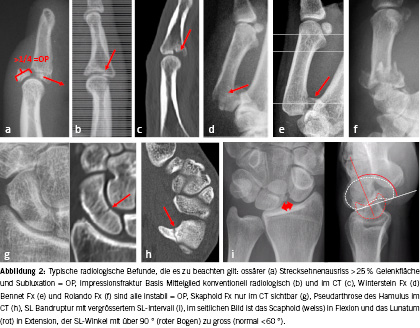

Die meisten Sportverletzungen an der Hand können einfach diagnostiziert und behandelt werden. Das Ziel dieses Artikels ist es, auf «Pitfalls» hinzuweisen, weniger bekannte Verletzungsmuster aufzuzeigen und auf die «Hitliste» häufig verpasster Diagnosen hinzuweisen. Eine topografische Differenzialdiagnose (Abb. 1) und radiologische Beispiele (Abb. 2) sollen Klarheit schaffen und an Vergessenes erinnern.

Bei Sportverletzungen im Bereich der Finger sind neben Frakturen meist der Kapselbandapparat (Kollateralbänder), die Strecksehnen, weniger die Beugesehnen betroffen. Inspektorisch ist bei Fehlstellungen, starker Schwellung, Achsenstossschmerz und Bewegungseinschränkung eine konventionell radiologische Abklärung zum Frakturausschluss indiziert. Dabei ist insbesondere auf eine exakte Exposition der seitlichen Projektion zu achten, um eine Impressionsfraktur der Basis des Mittelglieds ausschliessen zu können. Im Zweifelsfall muss eine CT-Untersuchung Klarheit schaffen. Undislozierte Frakturen ohne Gelenkbeteiligung können konservativ behandelt werden (sechs Wochen Intrinsic-plus-Schiene mit Einschluss der angrenzenden Gelenke).

Bei Schmerzen im Bereich des Daumen-Sattelgelenks sollte immer eine konventionell-radiologische Untersuchung (Daumen ap/seitlich mit Zentrierung auf das Sattelgelenk) durchgeführt werden und bei Unsicherheit ein CT erfolgen. Frakturen im Bereich der Basis des Metacarpale I (Bennet-, Rolando-, Winterstein-Fraktur) sind immer instabil und müssen operativ versorgt werden.

Die häufigste Läsion im Bereich der Strecksehnen ist eine Ruptur des Terminalzügels über dem DIP-Gelenk, auch Mallet-Finger genannt. Die Diagnose kann durch das sichtbar hängende Fingerendglied bereits klinisch gestellt werden. Es erfolgt eine konsequente Ruhigstellung des DIP-Gelenks in leichter Hyperextension in einer am besten durch die Ergotherapie angefertigten Schiene (Stack’sche Schiene) für acht bis zehn Wochen. Auch ossäre Strecksehnenausrisse können konservativ behandelt werden, wenn das Fragment weniger als 25 % der Gelenksfläche beträgt. Ist es allerdings grösser, disloziert oder das DIP-Gelenk subluxiert, muss eine Osteosynthese erfolgen. Weniger offensichtlich ist die Zentralzügelverletzung über dem PIP-Gelenk, die mit dem Elson-Test [4] (paradoxe Hyperextension des DIP-Gelenks bei Extension des flektierten PIP-Gelenks gegen Widerstand über dem Mittelglied) nachgewiesen werden kann. Es erfolgt eine konsequente Ruhigstellung mit einer PIP-Streckschiene für sechs Wochen. Bei verpasster Verletzung kann eine (fixierte) Knopflochdeformität mit zunehmender Flexionsfehlstellung in PIP- und Hyperextensionsfehlstellung im DIP-Gelenk resultieren, die nur mehr schwierig operativ behandelt werden kann.

Die Skaphoidfraktur ist die am häufigsten verpasste Fraktur und resultiert unbehandelt meist in einer Pseudoarthrose und längerfristig in einer Arthrose (SNAC wrist). Schmerzen nach einem Sturz auf das Handgelenk, die länger als zwei bis drei Wochen anhalten, sollten daher ernst genommen und abgeklärt werden. Bei Verdacht auf eine Skaphoidfraktur (Druckschmerzhaftigkeit in der Tabatière, distaler Skaphoidpol und dorsal-zentraler Druckschmerz) sollte mittels CT (oder MRT) eine Kahnbeinfraktur ausgeschlossen werden [7], da diese im konventionellen Röntgen oft nicht sichtbar ist. Eine nicht dislozierte Fraktur im mittleren oder distalen Drittel kann konservativ, alle anderen Frakturtypen (proximales Drittel, dislozierte Frakturen) müssen operativ behandelt werden. Im Fall einer konservativen Behandlung erfolgt eine Ruhigstellung im Skaphoidgips (Handgelenk und Daumeneinschluss) für acht Wochen mit folgender Konsolidationskontrolle im CT.

Die am häufigsten verpasste Bandverletzung im Bereich des Karpus ist die Ruptur des skapholunären Bands, da diese initial meist nur kurzfristig schmerzhaft ist. Nach einem schmerzarmen Intervall von mehreren Monaten resultiert ein karpaler Kollaps in zunehmenden Schmerzen und Arthrose (SLAC wrist). Bei einer Anamnese mit Handgelenkschmerzen dorsal zentral (auch Palpationsschmerz) sowie Blockadeerscheinungen und Schnappepisoden sowie positivem Watson-Test (schmerzhafte Ulnar-Radialduktion im Handgelenk, während Druck auf den distalen Skaphoidpol ausgeübt wird und dabei auftretende Krepitationsphänomene) sollte zum Ausschluss oder Nachweis dieser Verletzung ein Arthro-MRT durchgeführt werden. Konventionell-radiologisch besteht der Verdacht auf eine skaphoulnäre Bandruptur beim Auseinanderweichen von Skaphoid und Lunatum im pa-Bild sowie bei zunehmender Extensionsstellung des Lunatum und Flexionsstellung des Skaphoid im Seitenbild. Die Verletzung muss operativ mittels Bandnaht (erste drei bis sechs Wochen) oder mit einer Bandrekonstruktion behandelt werden.